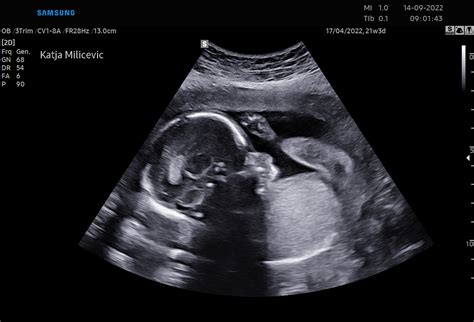

V tem obdobju se pričnejo razvijati tudi prstni odtisi, jezik in glasilke. Dojenček prične vaditi dihanje in požiranje plodovnice. Okoli 20. tedna nosečnosti, ko se opravi podroben ultrazvočni pregled, imenovan morfologija, je mogoče že opaziti spol otroka. Na morfologiji ginekolog pregleda razvoj posteljice in otroka ter oceni, ali obstajajo morebitni zapleti. V tem času mnoge nosečnice prvič občutijo nežne gibe svojega dojenčka, ki jih pogosto primerjajo s prhutanjem metuljevih kril. Ti gibi postajajo z nadaljevanjem nosečnosti vse bolj izraziti.